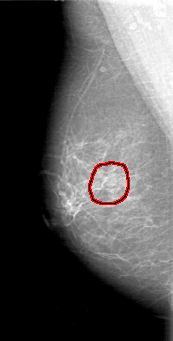

D_4027_1.RIGHT_MLO

RIGHT_MLO LINES 5101 PIXELS_PER_LINE 2581 BITS_PER_PIXEL 12 RESOLUTION 43.5 OVERLAY

FILE: D_4027_1.RIGHT_MLO.OVERLAY

TOTAL_ABNORMALITIES 1

ABNORMALITY 1

LESION_TYPE MASS SHAPE OVAL MARGINS OBSCURED

ASSESSMENT 0

SUBTLETY 3

PATHOLOGY BENIGN

TOTAL_OUTLINES 1

BOUNDARY